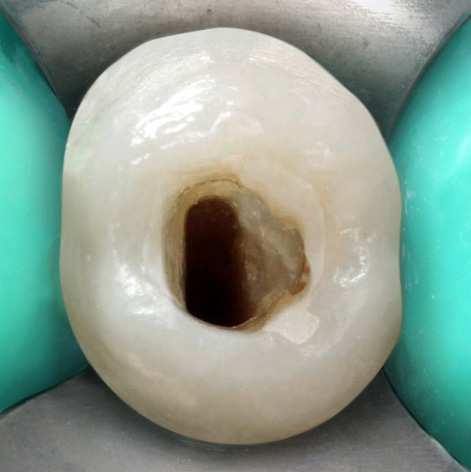

During the first appointment, the provisional material was removed, and the coronary access was refined with an inactive tip multilaminated bur (Endo Z, Angelus) (Figure 1B). This was followed by instrumentation of the cervical and middle thirds, after a calcium hydroxide associated with saline solution was used as intracanal dressing.

Figure 1B. Clinical aspects after refinement of the coronary access.